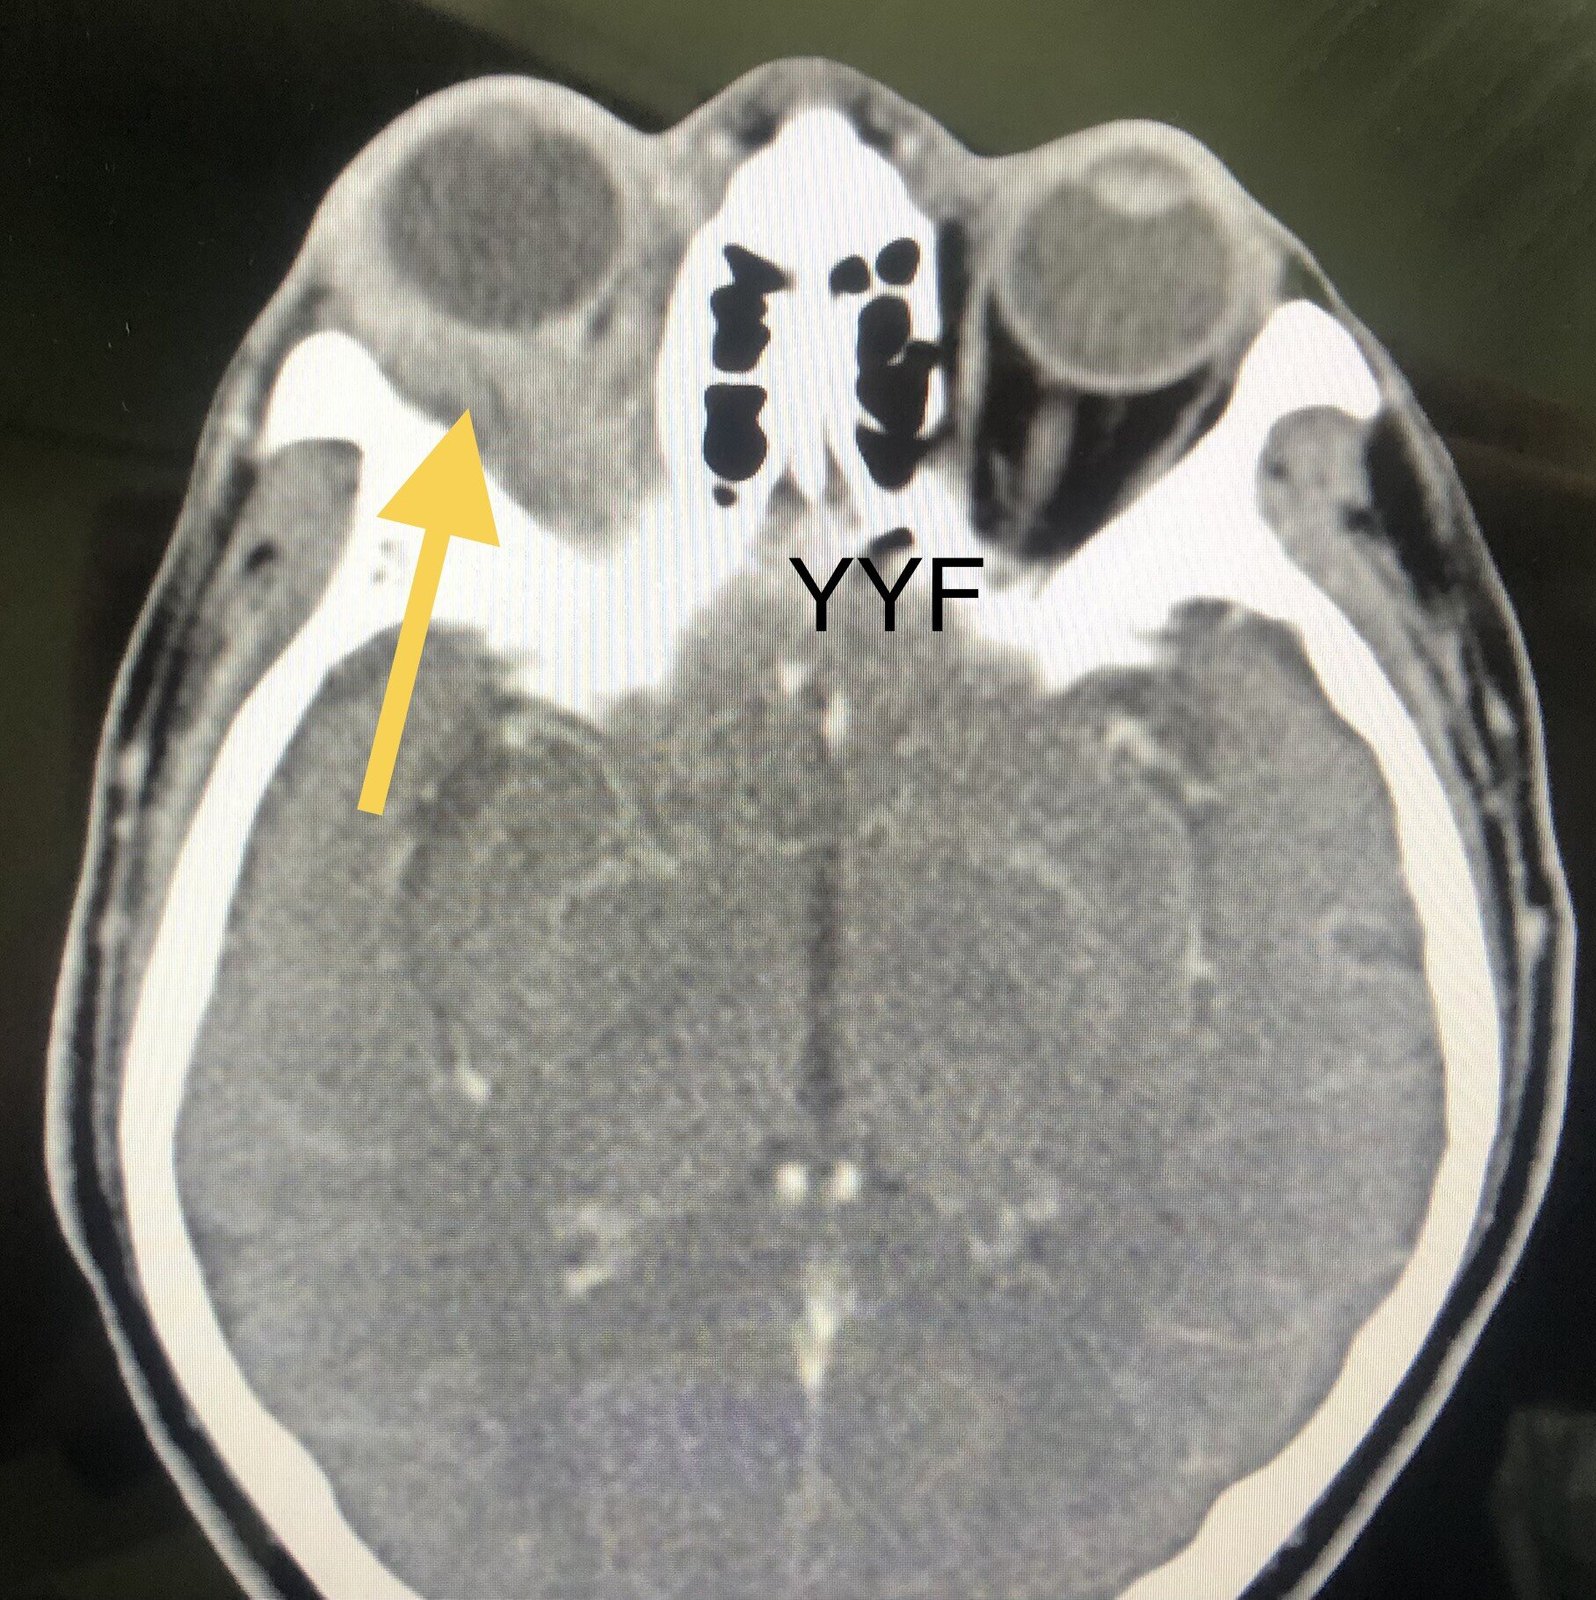

患者中年女性,因眼部肿胀,眼睑下垂,不时充血就医,拍片发现眼眶内弥漫性占位。

眼眶弥漫性占位

眼眶前段,有包绕眼球生长改变